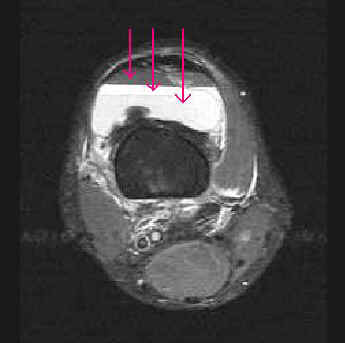

This axial STIR image demonstrates only three layers of the lipohemarthrosis. The most superior layer is fat, low in signal intensity due to the fat suppression technique. However, the separation between serum and dependant cellular components is best demonstrated on this sequence.